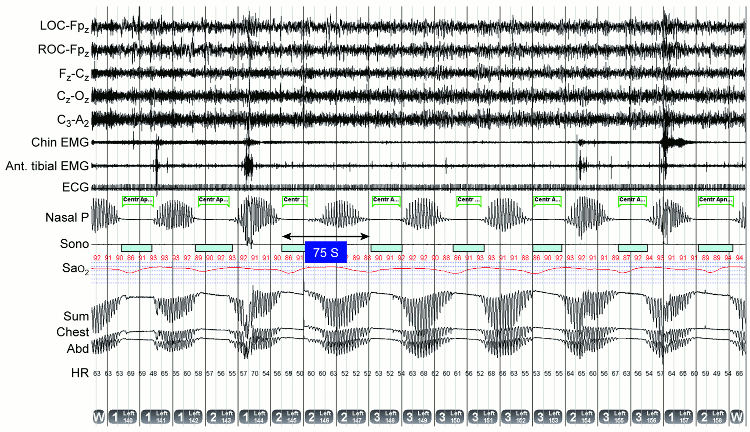

Home overnight oximetry can be useful to screen for the presence of sleep-disordered breathing in a high-risk population but it does not differentiate between central and obstructive events.[35] Therefore, polysomnography is required, and patients should be referred to a facility with polysomnographic testing and interpretation expertise.[36] The polysomnogram consists of close observation and recording of several channels of data during an entire night of sleep in a specialised facility. Measures include air flow, chest and abdominal movements, electroencephalogram, ECG, sub-mental and anterior tibialis electromyogram, oxygen saturation, and eye movements.[Figure caption and citation for the preceding image starts]: Cheyne-Stokes breathing: polysomnography demonstrating the characteristic waxing and waning of ventilation separated by central apnoeas (seen best in the nasal pressure transducer signal [Nasal P] and the abdominal [Abd], chest [Chest], and Sum respiratory impedance traces), resulting in almost sinusoidal desaturations in oxyhaemoglobin saturation. Cycle duration between events is 75 seconds; ECG demonstrates atrial fibrillation, both characteristic of a patient with advanced heart failureSleep-related breathing disorders. In: Krahn L, Silber M, Morgenthaler T. Atlas of sleep medicine. New York. Informa Healthcare, 2011. By permission of Mayo Foundation for Medical Education and Research. All rights reserved [Citation ends].